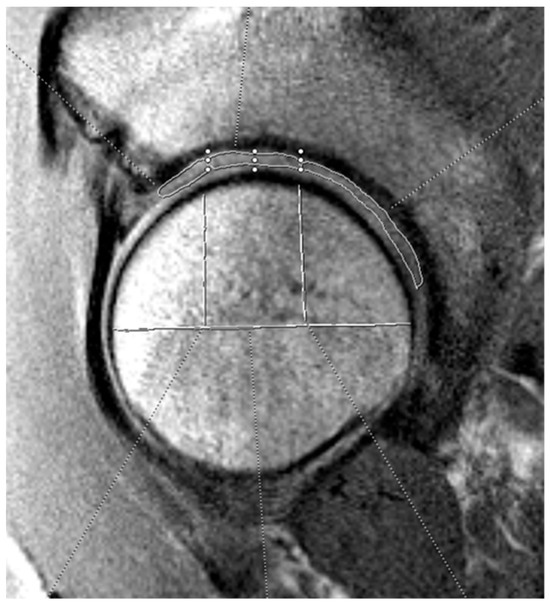

The three independent, blinded reviewers analyzed T2 mapping on the optimal sagittal MRI cut using the Syngo.via T2 mapping software (Siemens Healthineers, Erlangen, Germany). Reviewers included an orthopedic surgery resident (A.P.) and two medical students (C.A., K.J.) supervised by a board-certified musculoskeletal radiologist (C.H.). For T2 analysis, the acetabular and femoral head cartilage were each divided into anterior, superior, and posterior zones. See Figure 1 and Figure 2 for a visual representation of this division in the mapping software. The average T2 mapping value for each respective zone on the acetabulum and femoral head were measured two times by each of the three reviewers and the average of these values was taken. Intraclass correlation values were obtained to confirm appropriate inter-observer agreement. Hip morphology measurements were recorded from CT scans using 3D reconstruction and measurement software (HipMap, Stryker, Kalamazoo, MI, USA). Measurements included alpha angle, lateral central edge angle (LCEA), acetabular coverage, femoral version, acetabular version at 12 o’clock, 2 o’clock, and 3 o’clock, femoral neck-shaft angle (FNSA), and Tönnis angle.

Figure 2. Example of femoral head cartilage T2 mapping on a sagittal MRI. The measurements were divided into three zones (anterior, superior, and posterior). The horizontal white line bisects the femoral head, and the vertical lines split the joint surface into 3 zones: anterior (left), superior (middle), and posterior (right). The three zones on the femoral head cartilage are drawn by free-hand technique based on these divisions.